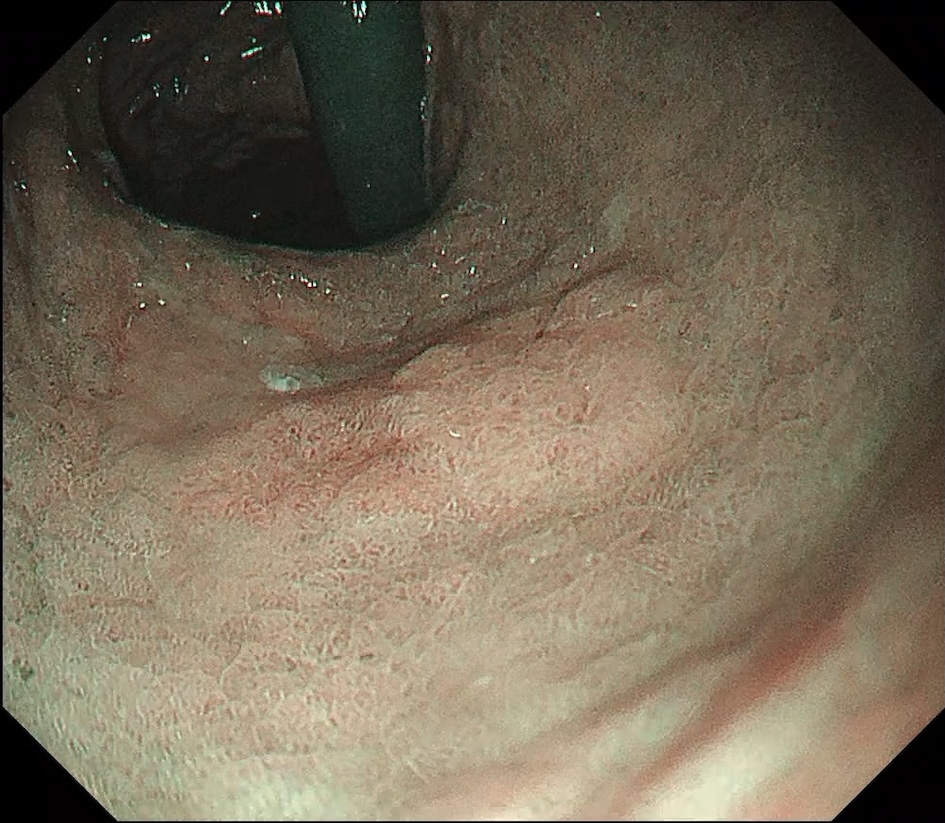

• NBI観察①(中遠景)

強調設定:B8

図3

NBI観察:病変は周囲粘膜と比較して褪色調を呈し、白色光観察で認めた淡い発赤部に一致してbrownish areaを認める。